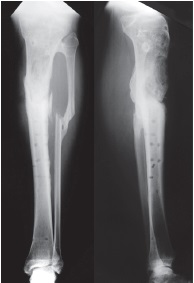

We first visited this patient after plate removal still presenting a draining sinus tract. The diagnosis was a Cierny-Mader type III osteomyelitis. We operated this patient in six months after the injury. A partial anterior resection of a 4 cm long segment was necessary. We performed a partial osteotomy of the anterior aspect of the tibia for setting up an anterior fragment to be transported from proximal to distal (Figure 6). The continuity of the posterior cortex was maintained. We finally applied the Ilizarov apparatus to ensure stability; the fragment was fixed with two 1.8 mm olive K-wires and connected to a half-ring for progressive bone transport (Figure 7, 8). The frame was removed less than in 5 months after the surgery when union was achieved. The patient’s last follow-up was at 4 years after frame removal with no reported recurrence of infections or other complications (Figure 9).

Figure 8. X-ray showing the split fragment connected to a half-ring for progressive distraction

Figure 9. X-ray at the last follow-up shows the fragment filling the previous defect and remodeling of proximal bone regenerate